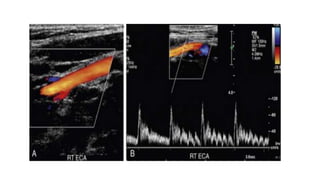

• The ECA, which supplies the muscular bed of the scalp, typically

demonstrates completely absent or very low velocity end-diastolic flow.

Although the amount of diastolic flow in the ECA may vary from patient

to patient, it should be symmetric right to left and less than the diastolic

flow in the ICA or CCA.

• An early diastolic notch followed by a short reversal of flow in early

diastole is often seen in the ECA.

• Differentiation of the ICA from the ECA is critically important to avoid

misinterpretation of a stenosis in the ECA as a more clinically significant ICA

stenosis.

• The best method of identifying the ECA is by visualization of branches arising

from the vessel .

• The ICA virtually never gives rise to branch vessels in the neck.

• Temporal tapping over the ophthalmic artery will generate sharp, spike-like

deflections in the waveform of the ECA during diastole

• The CCA,ICA, and ECA demonstrate distinct characteristic waveform patterns. • All segments of the extracranial carotid arteries normally demonstrate a sharp systolic upstroke and thin spectral envelope, the amount of diastolic flow varies in each vessel. • The ECA, which supplies the muscular bed of the scalp, typically demonstrates completely absent or very low velocity end-diastolic flow. Although the amount of diastolic flow in the ECA may vary from patient to patient, it should be symmetric right to left and less than the diastolic flow in the ICA or CCA. • An early diastolic notch followed by a short reversal of flow in early diastole is often seen in the ECA.

• Differentiation ofthe ICA from the ECA is critically important to avoid misinterpretation of a stenosis in the ECA as a more clinically significant ICA stenosis. • The best method of identifying the ECA is by visualization of branches arising from the vessel . • The ICA virtually never gives rise to branch vessels in the neck. • Temporal tapping over the ophthalmic artery will generate sharp, spike-like deflections in the waveform of the ECA during diastole